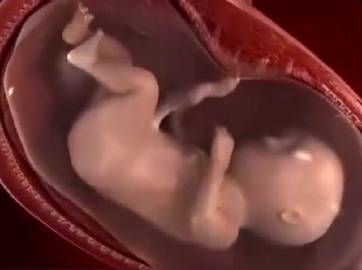

孕妈在怀孕第七个月的时候,孕妇吃的东西会越来越多,体重上升增幅很大,这是因为胎儿在这个时期需要吸收更多的营养来供自己成长,在这个时候最忌讳的就是孕妇节食。

怀孕第八个月

孕妈在怀孕八个月的时候,肚子会有发紧的现象,大腿和腹部会出现妊娠纹,此时孕妈的情绪不稳定,容易烦闷焦躁,睡眠严重不足。

怀孕第九个月

怀孕第九个月时,由于子宫占满了整个腹腔,所以对孕妈的食欲有很大影响,有些孕妇肚子非常大,可能会压迫到心脏,出现心悸气短的情况,而且还会有腹痛的感觉。这个时候孕妇身边不能离开照顾的人,防止出现紧急状况。

怀孕第十个月

孕妈怀孕第十个月的时候,孩子即将就要来到这个世界,孕妈在生完孩子之后子宫就会慢慢自然收缩变小。